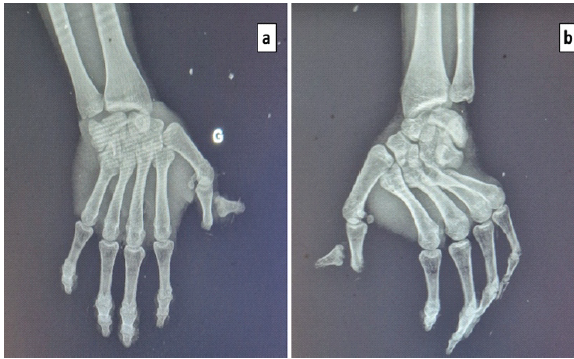

Standard radiographs (anteroposterior and lateral views) of the left hand demonstrated a volar convergent, spatulate CMC dislocation with an associated posterolateral dislocation of the thumb at the interphalangeal joint (Fig. 2).

Figure 2: Pre-operative radiographs. Anteroposterior and lateral views showing a volar convergent spatulate carpometacarpal dislocation with an associated posterolateral dislocation of the thumb at the interphalangeal joint.